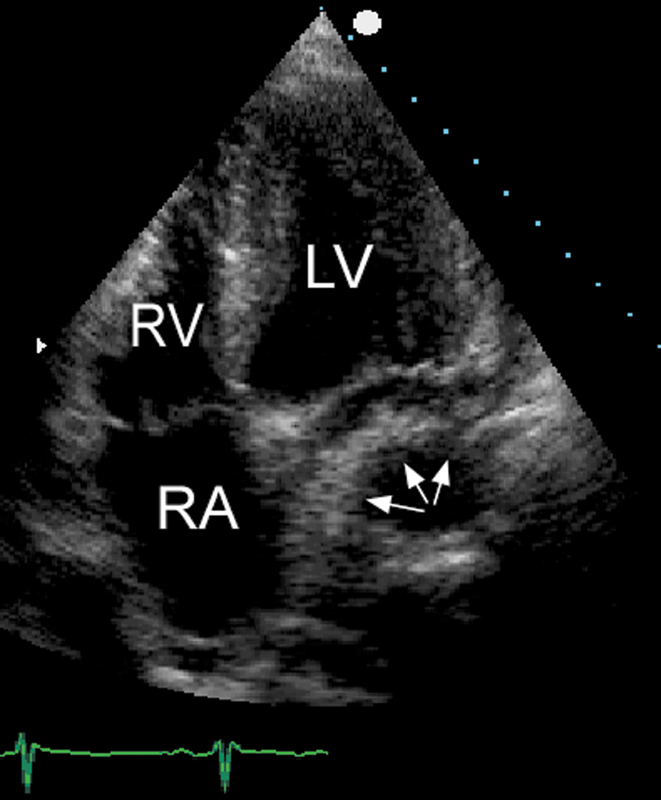

فحوصات تشخيصية لبعض امراض القلب والشرايين التاجية